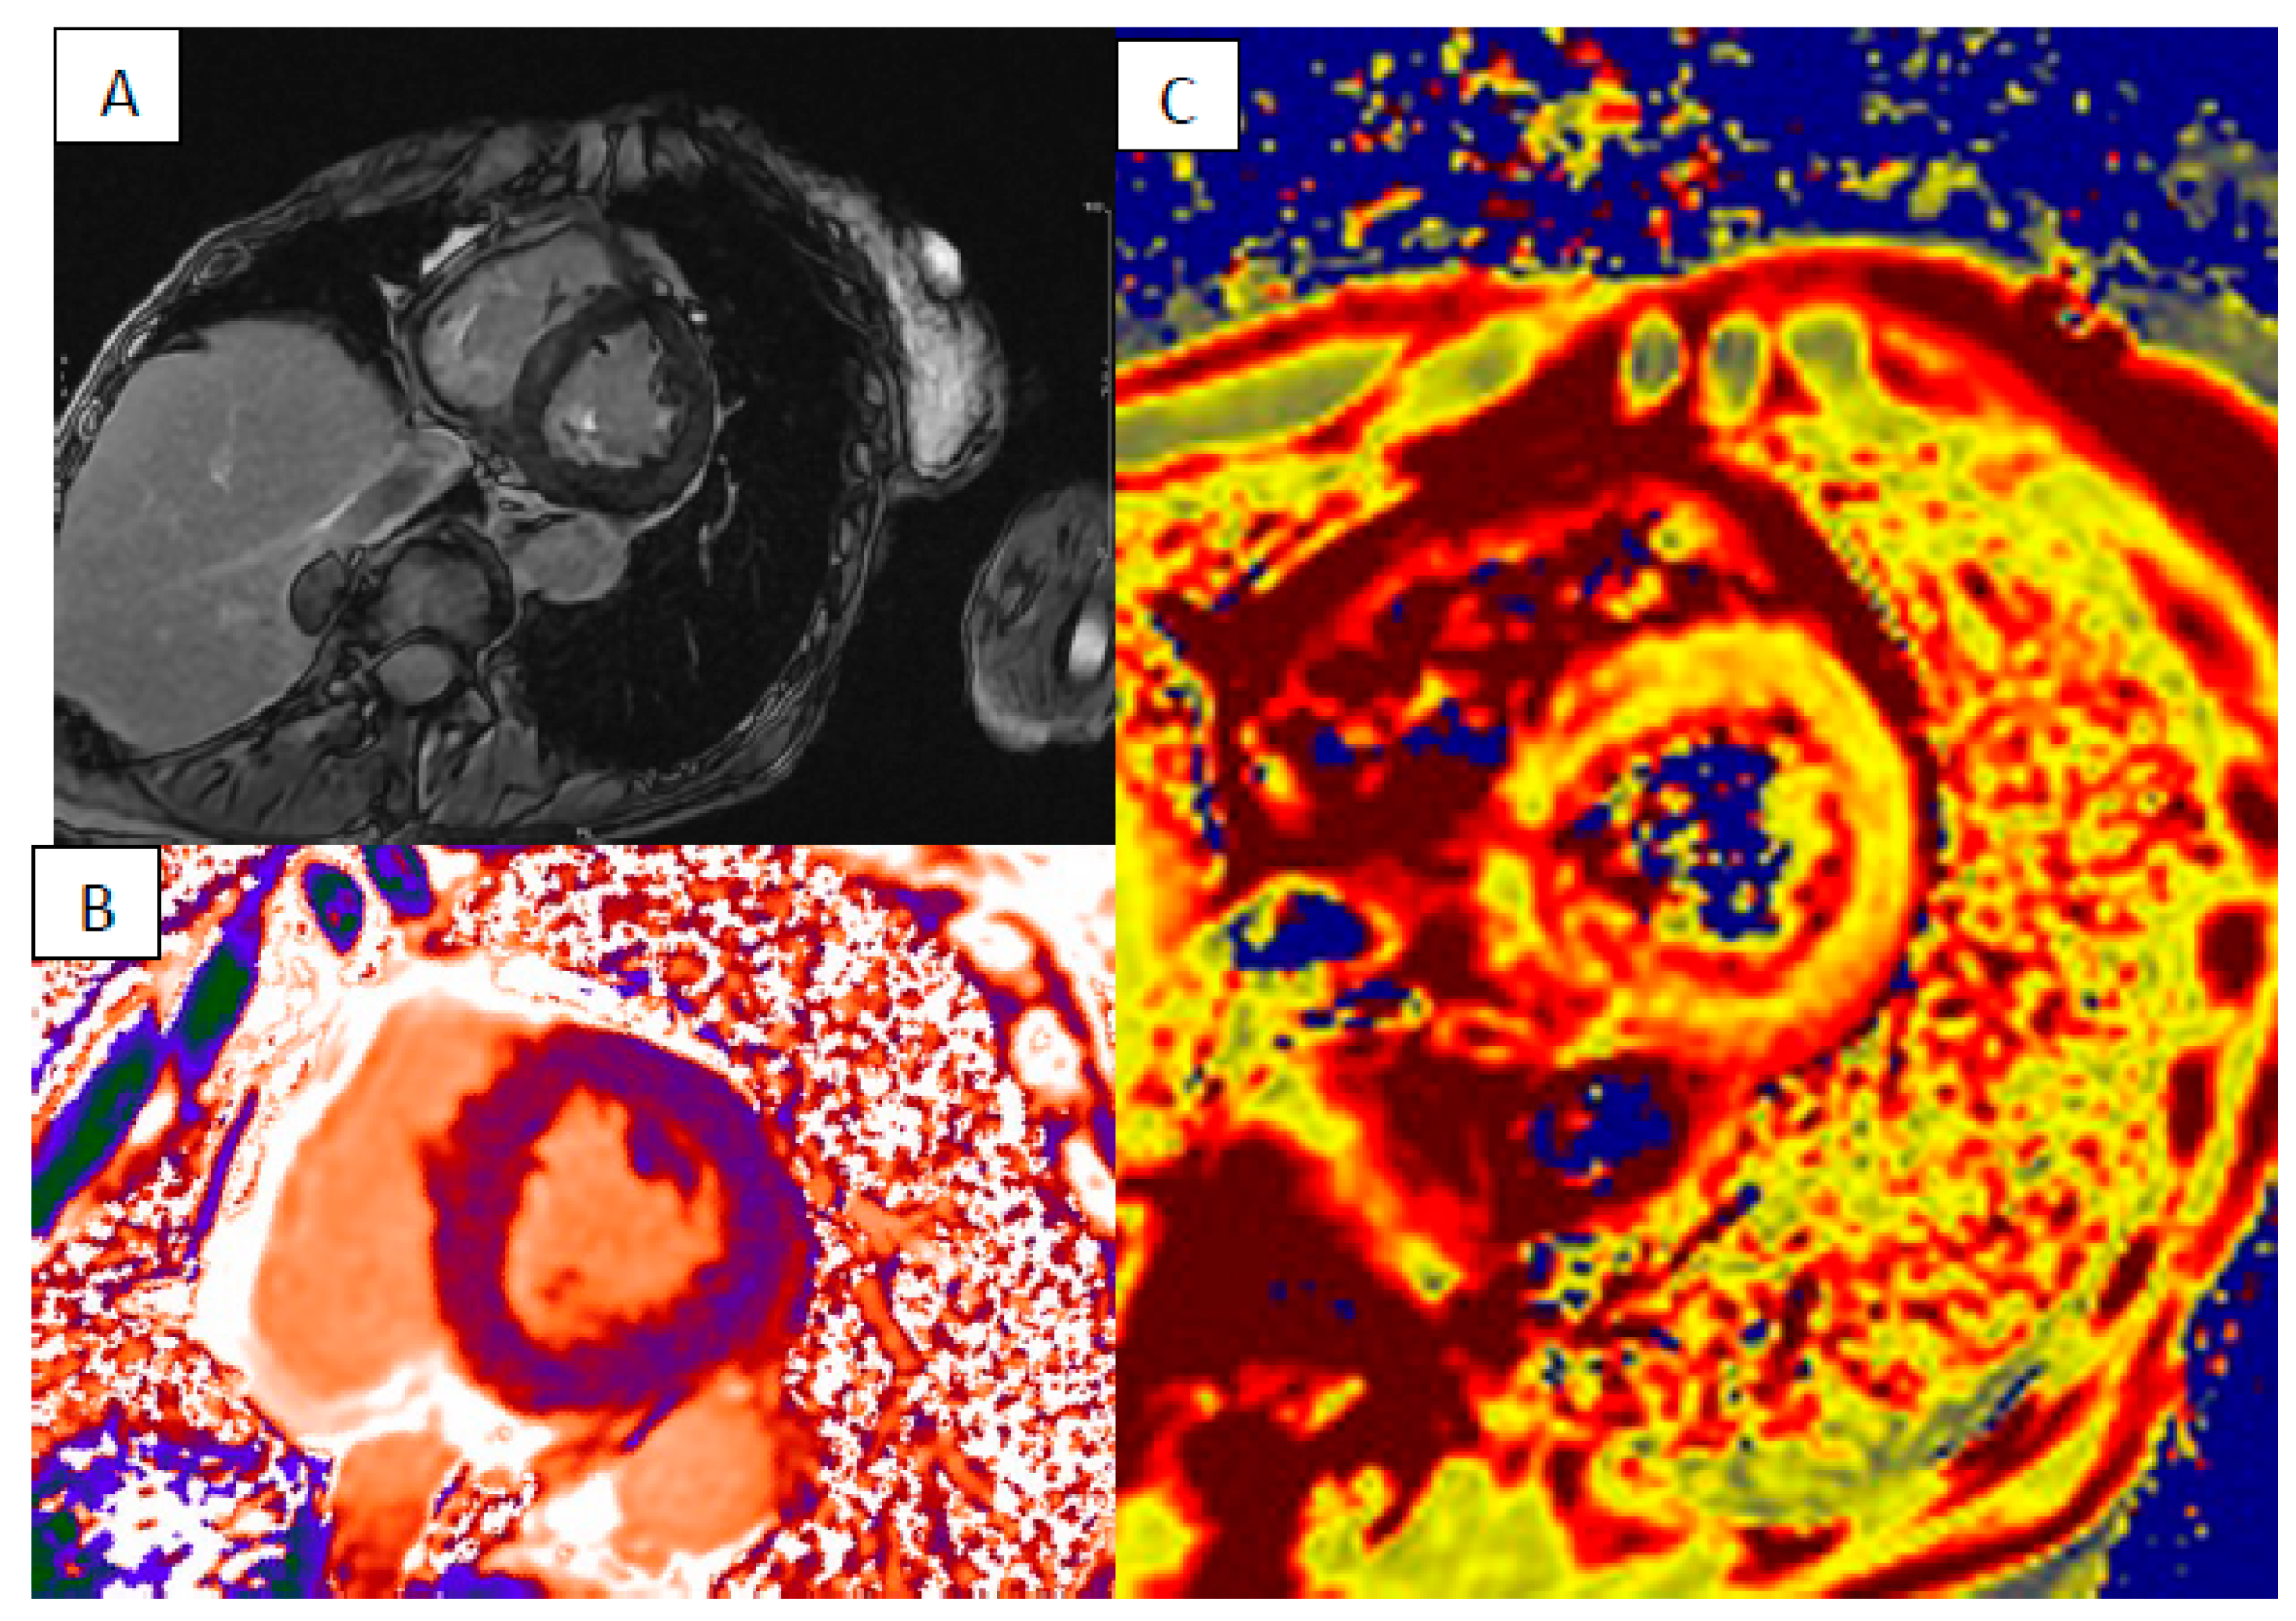

3. Cardiac Sarcoidosis